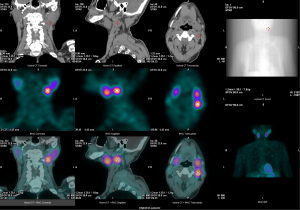

Further localization of the suspected ectopic parathyroid lesion was performed using single-photon emission computed tomography/computed tomography (SPECT/CT) with 99mTc-sestamibi parathyroid scintigraphy. No definitive uptake was noted in the typical anterior parathyroid regions. However, an ovoid, slightly hyperdense lesion was identified in the left cervical level II–III region, exhibiting patchy areas of lower density. These imaging features were highly suggestive of an ectopic parathyroid adenoma (Figure 5). Although not available in our institution at that time, 18F-fluorocholine positron emission tomography (PET)/CT has been increasingly recognized as a highly sensitive imaging modality in patients with ectopic or inconclusive parathyroid adenomas.

The localization of ectopic parathyroid tissue frequently lies beyond the conventional field of view of routine cervical ultrasound or CT, limiting the sensitivity of these singular imaging modalities. In the present case, parathyroid ultrasound examination to detect any abnormalities, underscoring the inherent constraints of standard cervical ultrasonography in identifying ectopic parathyroid adenomas. Sole reliance on individual imaging techniques often proves insufficient to encompass the intricate anatomical variability of ectopic parathyroid glands, predisposing to missed diagnoses or misinterpretations. For patients with suspected ectopic parathyroid tissue, the integration of cervical and mediastinal 99mTc-sestamibi SPECT/CT substantially enhances detection rates, with reported sensitivity reaching up to 90% and specificity approximating 98% (11). Moreover, 4D-CT serves as a valuable second-line modality, employing dynamic vascular contrast enhancement to delineate characteristic adenoma perfusion patterns—arterial phase hyperenhancement followed by delayed washout—with diagnostic accuracy ranging between 85% and 95% (12). In this case, a combined preoperative imaging approach utilizing SPECT/CT fused with 4D-CT could further refine lesion localization, minimize surgical exploration extent, and mitigate risks of erroneous intervention. Our approach is consistent with current international guidelines. The American Association of Endocrine Surgeons (AAES, 2016) and the European Society of Endocrinology (ESE, 2022) emphasize the importance of concordant dual imaging prior to performing focused or minimally invasive parathyroidectomy (13,14). In this case, both contrast-enhanced CT and 99mTc-sestamibi SPECT/CT demonstrated findings consistent with an ectopic parathyroid adenoma, thereby satisfying the guideline-recommended principle of dual concordant imaging. Although 18F-fluorocholine PET/CT was not available at our institution, our diagnostic pathway adhered to accepted standards of care. Future incorporation of PET/CT imaging, where available, could further improve the detection and localization of ectopic adenomas and minimize diagnostic uncertainty. Notably, the markedly elevated PTH level of the patient (1,912 pg/mL) and precipitous postoperative decline validate the completeness of resection and exemplify the utility of multimodal imaging in guiding precise surgical management.